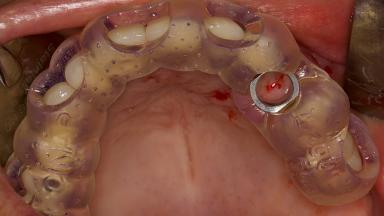

Digitally Guided Sinus Floor Elevation

In this short microlearning module on digitally guided sinus floor elevation, we delve into a specialized aspect of the digital workflow for implant-guided surgery, focusing on the use of digital guides in the sinus floor elevation technique.

• explore the intraoperative use of digital guides in SFE